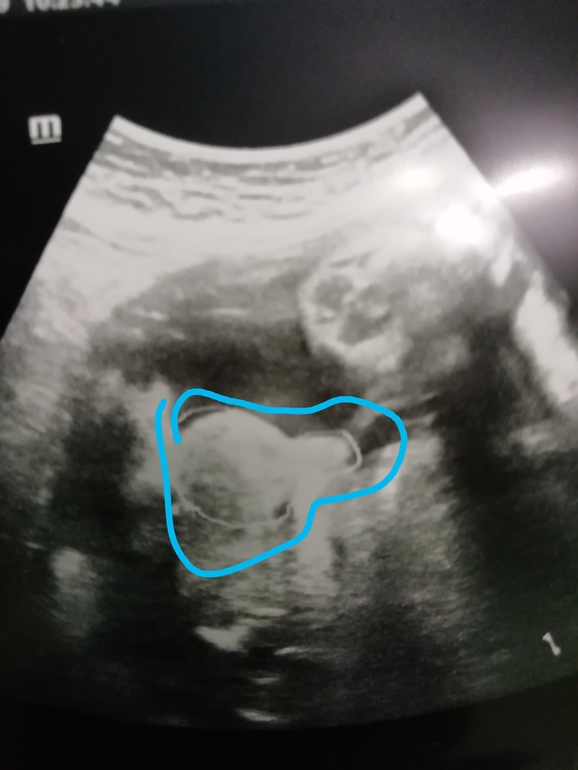

А вот и малыш, не похож ни на брата, ни на сестру совсем 💙💙💙

💙Ну а тут видно, что мужик 🥒